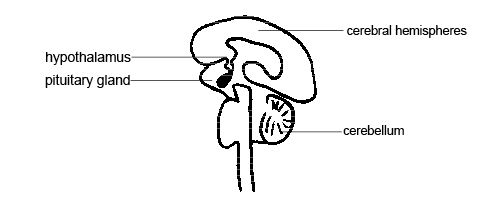

Hypothalamus is of the size of a pearl. It performs several important functions. It sends signals to the brain which activates adrenaline flowing that wakes you up in the morning. The hypothalamus is also an important emotional center, controlling the molecules that make you feel sad, exhilarated, or furious.

The hypothalamus is a small structure located between the pituitary gland and thalamus. It is a vital region of the central nervous system. It is responsible for hormone production and in stimulating several biological processes in the body.

The hypothalamus has three main regions:

- Anterior region

This region of the hypothalamus is also termed as the supraoptic region. Supraoptic and paraventricular nuclei are the major nuclei. These are responsible for secretion of various important hormones like;

- Middle region

This region of hypothalamus is also termed as the tuberal region. Arcuate nuclei (releases growth releasing hormone – GHRH which stimulates the pituitary gland to release growth hormone) and the ventromedial nucleus (aids in controlling appetite) are the key nuclei. This tuberal region plays a major role in the growth and development of the body.

- Posterior region

This region of hypothalamus is also termed as the mammillary region. And is believed to be involved in memory function. The posterior hypothalamic nucleus is responsible for regulation of body temperature by causing shivers in the body and preventing sweat release.

Hypothalamus

Undersurface of the brain.